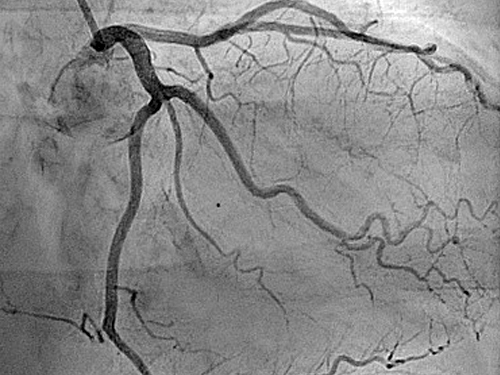

Coronary Angiogram

A coronary angiogram is a diagnostic X-ray procedure that uses a contrast dye to identify blockages or narrowing in the heart’s blood vessels. During the procedure, a catheter is inserted into an artery in the groin or arm and guided to the heart, where dye is injected to make the arteries visible on X-ray. It helps diagnose conditions like coronary artery disease and is essential for planning treatments.